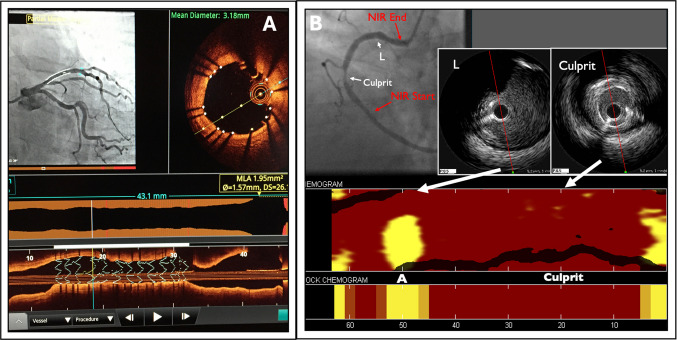

回顾的目的:我们试图回顾各种冠状动脉内成像方式(血管内超声、光学相干断层扫描和近红外光谱)以及支持其在临床实践中应用的最新证据。最近的发现:越来越多的证据表明,在改善经皮冠状动脉介入治疗(PCI)的结果方面,成像引导策略优于单独的血管造影术。一个有趣的和有前途的应用是使用这些设备来识别和治疗高风险或易损斑块。这些模式的应用在特殊的临床情况也进行了审查。血管内成像提供了血管造影以外的信息,可用于改善PCI患者的预后。新出现的证据已被纳入最新的实践指南建议。未来的研究正在进行中,以确定血管内成像对易损斑块的检测和治疗的益处。

Recent findings: There is an increasing body of evidence that demonstrates that imaging-guided strategies are superior to angiography alone to improve outcomes of percutaneous coronary intervention (PCI). An intriguing and promising application is use of these devices to identify and treat high-risk or vulnerable plaques. The application of these modalities in special clinical scenarios is also reviewed. Intravascular imaging provides information beyond the angiogram that can be used to improve patient outcomes during PCI. The emerging evidence has been incorporated into the most recent practice Guideline recommendations. Future research is underway to establish the benefit of intravascular imaging for detection and treatment of vulnerable plaques.